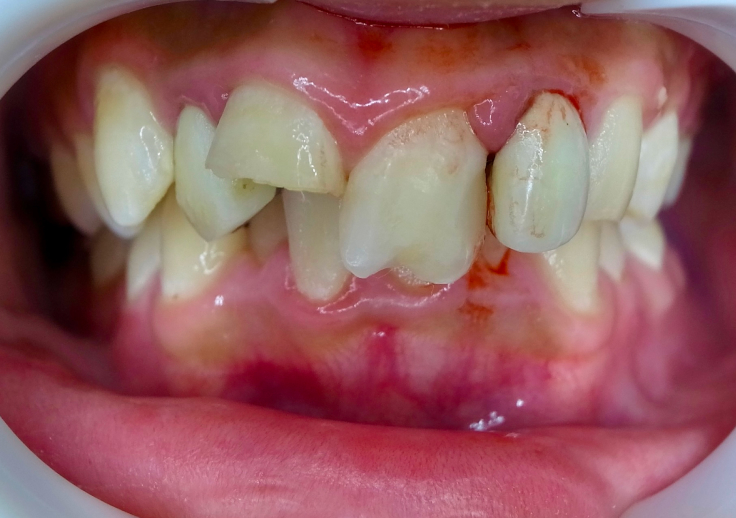

むし歯や転倒などにより、歯が欠けたり折れたりすることがあります。

「痛みがない」「欠け方が小さい」といった理由で放置するのは危険です。

欠けた部分から細菌が入り込み、むし歯や感染が進行することがあります。

また、外傷の影響で歯だけでなく、歯ぐきや顎の骨にまでダメージが及んでいる場合もあります。

歯は互いに支え合って並んでいるため、

1本のトラブルを放置すると、歯並びや噛み合わせが乱れるなど、

お口全体に悪影響が広がってしまいます。

歯がグラグラと揺れ始める

冷たい甘いもので歯がしみる

噛んだときに痛みが出る

歯が脱臼し最終的に抜けてしまう

神経が傷つき、歯が変色する

歯ぐきから出血しやすくなる 欠けた部分に歯科用の樹脂(コンポジットレジン)やセラミックを接着し、形を整える治療です。